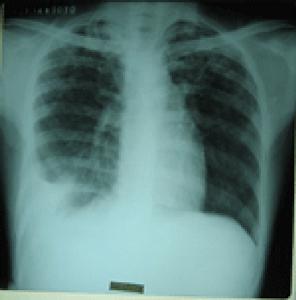

(1)X線胸片:乾性胸膜炎患側僅肋膈角變頓,滲出性胸膜炎中等量以上積液可見大片均勻緻密影,其上緣呈從外上向內下的弧形,肋膈角消失,膈影及心影不清。大量積液時縱膈向健側移位,肋間隙變寬,膈肌下降。